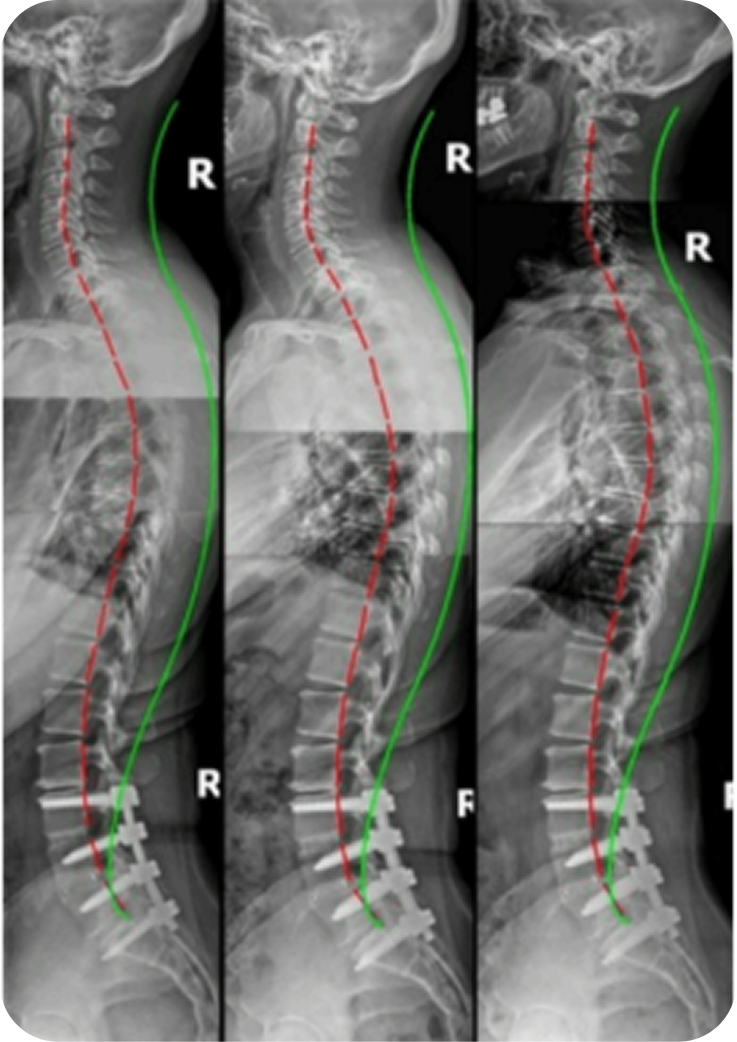

O tratamento corrige desalinhamentos que comprimem o nervo ciático, reduzindo a dor irradiada e devolvendo estabilidade à região lombar.